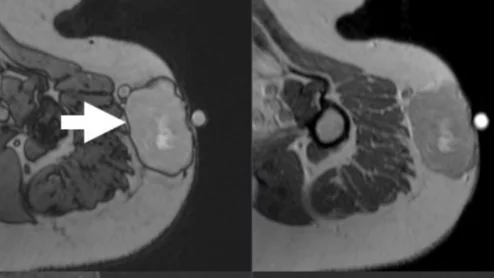

COVID-19 medical imaging examples of various clinical presentations. SARS-CoV-2 clinical imaging presentations.

This image gallery shows what the various clinical presentations associated with the COVID-19 and long COVID that have been documented during and after coronavirus pandemic.